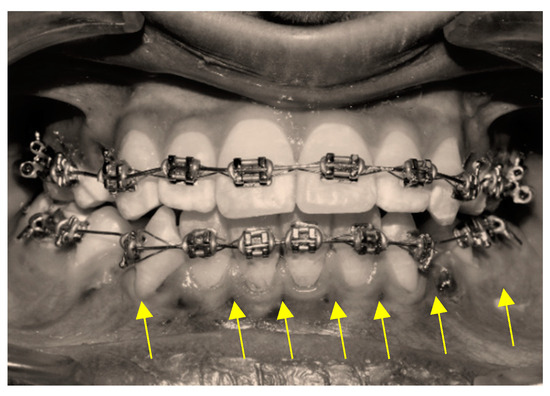

2.3.1. Piezocision Procedure (PZ)

2.3.2. Micro-Osteoperforation Procedure (MOP)